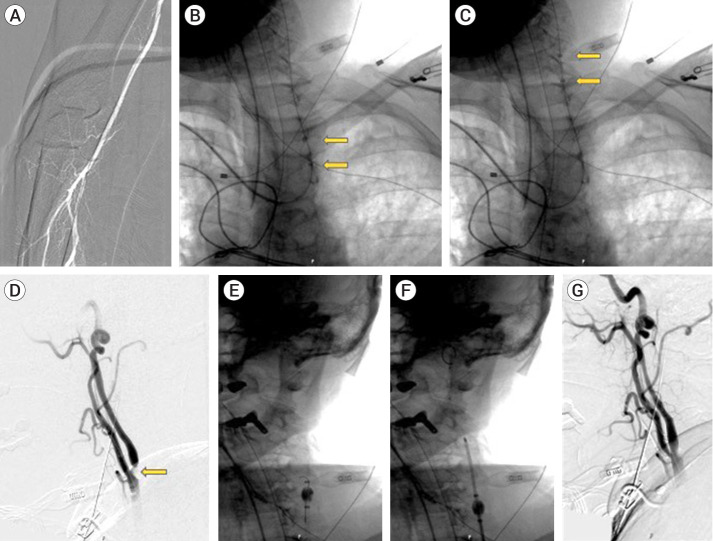

Intro: There is a growing preference among neurointerventionalists for transradial access (TRA) over transfemoral access (TFA) due to improved patient satisfaction, recovery time and reduced access site complication, but using balloon guide catheters (BGCs) in the radial artery remains a challenge. We report our experience in successfully using the 0.087" inner diameter Walrus BGC without a sheath via the radial artery for non-emergent neurointerventions.

Objective: Describe the technique for safely accessing the radial artery using the sheathless Walrus balloon guide catheter.

Methods: A retrospective chart review of thirteen consecutive patients who underwent intervention with radial artery access with a sheathless Walrus BGC was performed.

Results: All twelve procedures were performed successfully with no instances of conversion from TRA to TFA. There were no significant procedural or access site complications. The mean radial diameter was 2.51 mm.

Conclusions: The Walrus 0.087" ID BGC is an effective tool that can safely be used via the radial artery using a sheathless approach, which helps to maximize the size of the catheter that can be used. This is the first instance of our knowledge of this technique being utilized for neurointerventions and therefore could be used to expand the indications for TRA for a wider range of procedures.